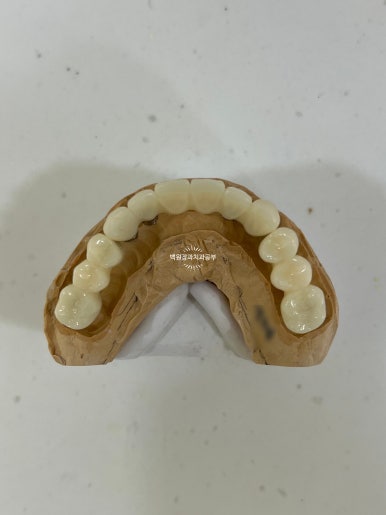

최종 보철물.. 드디어 제작이 되었습니다.

사실 정말 정말 감동적인 순간입니다... 우리 환자분께서 이 날만을 얼마나 기다리셨을까요.....

전체 임플란트를 완성하는데 전체 치료기간은 약 8개월 정도 걸렸습니다. 상당히 빨리 졸업하신 편이에요!

정면에서 보시면 임시 치아와 다르게 훨씬 깊이감 있는 색상으로 제작되어 자연스럽고, 완성도 있는 형태를 확인하실 수 있습니다.